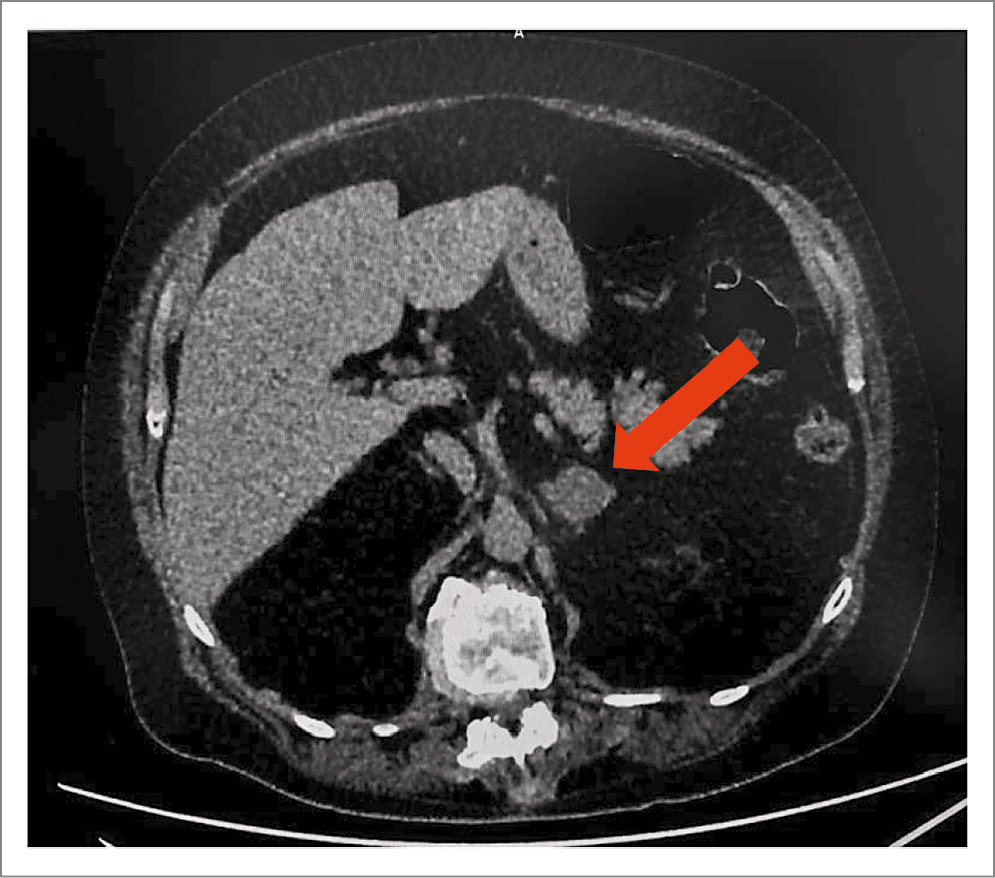

Проведена КТ органов брюшной полости: в паренхиме тела и латеральной ножке левого надпочечника – аденома округлой формы диаметром до 22 мм нативной плотностью до +3 HU, с накоплением контраста до +55 HU, с вымыванием до +22 HU (абсолютный индекс вымывания – 60%, относительный индекс вымывания – 48%); рис. 2.

Рис. 2. КТ брюшной полости и забрюшинного пространства от 25.03.2023: аденома.

С целью исключения гормональной активности выявленного образования надпочечника исследованы уровни альдостерона 68 пг/мл (в покое 41,71–208,9) и ренина 14,98 нг/мл/ч (0,32–1,84). Определение метанефринов не проводилось ввиду низкой плотности образования.